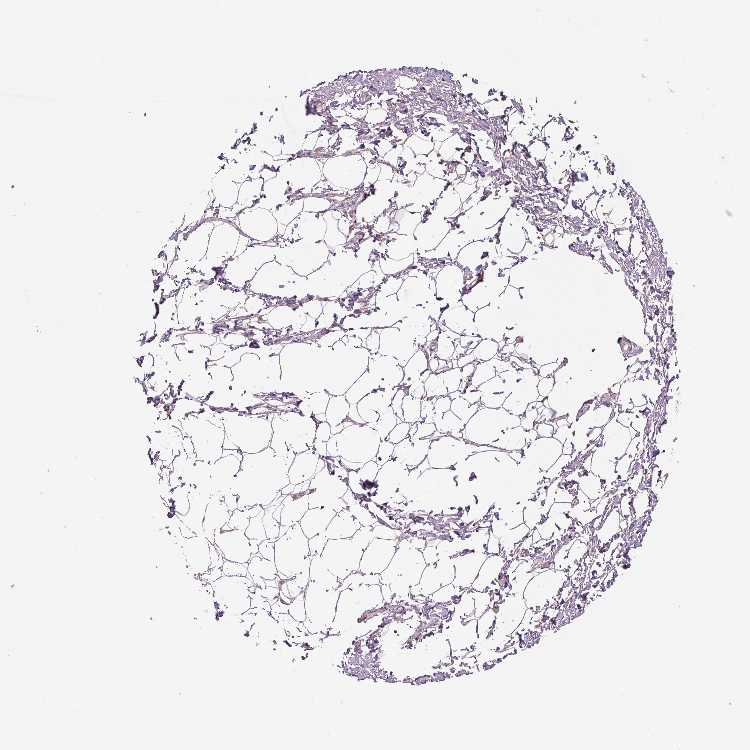

Adipose tissue